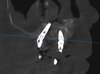

· Выполнение сложных костно-пластических операций, включая латеральный синус-лифтинг с одномоментной имплантацией.

· Костная пластика: латеральный и крестальный синус-лифтинг, направленная костная регенерация (НКР), аугментация альвеолярного гребня.

· Цифровые технологии: Работа с цифровыми хирургическими шаблонами, планирование в 3D-протоколах.

· Дополнительные методы: Применение пьезохирургии (Acteon), лазерной хирургии (Er:YAG, Nd:YAG).